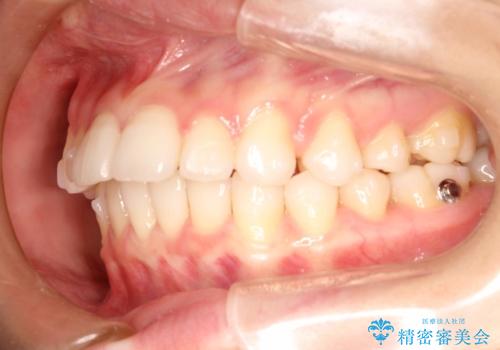

インビザラインで出っ歯を改善する 抜歯をしないinvisalign治療

- 非抜歯・遠心移動による前突の改善をマウスピースにて計画した。

非抜歯矯正の場合、大きく前歯を下げることはできませんが、奥歯の遠心移動や歯のサイズダウンにより歯軸を立て、見かけ上の出っ歯感をある程度改善することができます。